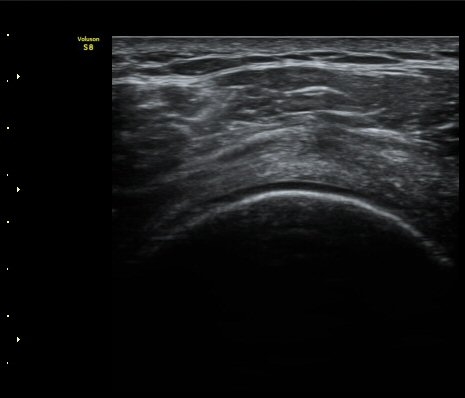

±Ø»ó°ÇÀÇ È¾´Ü¸é°Ë»ç¿Í Á¾´Ü¸é°Ë»ç¿¡¼­ ±Ø»ó°Ç³»¿¡ °í¿¡°í ¼®È¸È­ À½¿µÀÌ

°üÂûµÈ´Ü(»çÁø 1, 2).

¾î±ú¸¦ 90µµ ¿ÜÀüÇÑ »óÅ¿¡¼­ À­ÆÈÀ» ³»È¸ÀüÇÏ´Ï °ßºÀ¿À±¸µ¹±â Àδ밡 Ç¥ÃþÀ¸·Î

ÀüÀ§µÈ´Ù(÷ºÎ ÆÄÀÏ µ¿¿µ»ó 1)